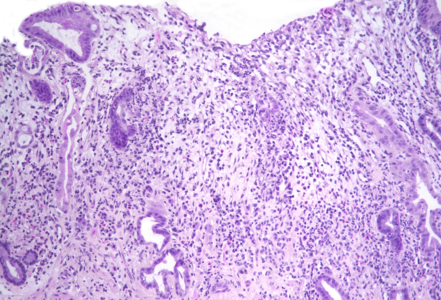

Gastric biopsies from a 68-year-old male with history of lung cancer.

Immune checkpoint inhibitor associated gastritis.

Histology showed an extremely altered gastric mucosa, with architectural distortion by glandular atrophy, degenerative epithelial changes, erosions and an expanded oedematous lamina propria (PANEL A-C). On higher magnification, the lamina propria contained a mixed inflammatory infiltrate, characterized by lymphocytes, plasma cells, eosinophils and neutrophils, focally with abscess formation. We observed withering glands lined by flattened eosinophilic epithelium, occasionally containing apoptotic debris (PANEL D-E); in other areas, little atrophic neuroendocrine nests were found (PANEL F). In summary, there was a severe acute inflammation and signs of acute epithelial injury highly suggestive of a drug-induced gastritis, consistent with injury due to pembrolizumab.